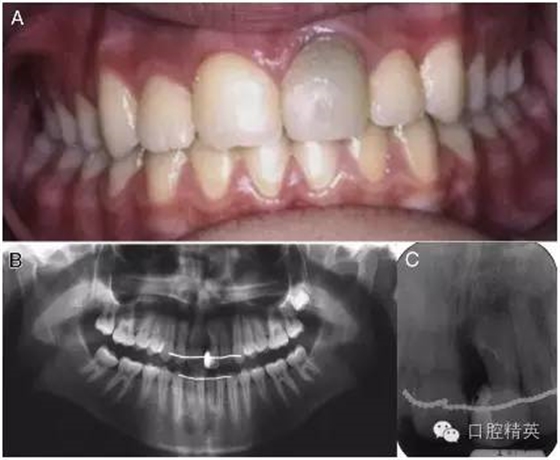

圖 4 十年后復查發(fā)現(xiàn),患牙依然保存了牙髓活力,并且全口牙齒前后牙咬合關系正常,復合樹脂修復的效果也令人滿意。(A)口內正面像。(B)x 線全景片。(C)根尖片。

做過手術 10 年之后,患牙剩余部分保存完好。通過問診、牙髓活力測試和 x 線根尖片,患牙的牙髓活力最終被確診為正常。此外,復合樹脂修復體也是完整的,而且通過口內臨床檢查和 x 線片檢查,未發(fā)現(xiàn)有患牙有繼發(fā)齲的跡象。因為原來的樹脂修復材料已經(jīng)變色,患者被建議重新做一下此牙的修復(圖 4)。